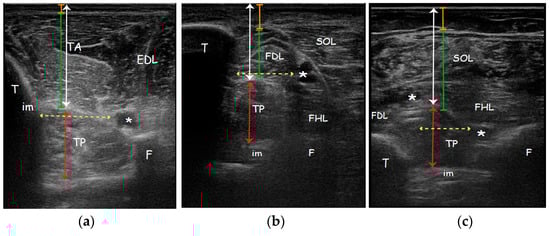

We evaluated MT and MD that were measured as the distance between superficial and deep aponeuroses and between superficial aponeurosis and the line separating the dermis from fat, respectively.

Cross-sectional area (CSA) was measured only in the posterior approach since only this view ensures a complete visualization of the TP and it was represented by the total area of the TP muscle surrounded by the muscle fascia in a transverse scan perpendicular to the direction of muscle fibres [45]. Safety window (SW), defined as the distance between structure that must be avoided during needle insertion to prevent a neurovascular damage, in AA was calculated between tibialis anterior artery (adjacent to the branches of fibular nerve) and medial side of the tibia. SW in MA was measured between tibialis posterior artery and posterior side of the tibia. SW in PA was found between tibialis posterior artery and fibular artery (adjacent to the fibula and deep to the flexor hallucis longus) (Figure 2). Safety window was calculated only on the affected side.

Figure 2.

Real ultrasound images of a patient enrolled in the study, affected side. Parameters measured with ultrasonography evaluating the (a) Anterior approach; (b) Medial approach; (c) Posterior approach. Orange line: subcutaneous tissue thickness; Green line: overlying muscle thickness; White arrow: TP muscle depth; Red arrow: TP muscle thickness; Yellow dotted arrow: safety window. Abbreviations: TA tibialis anterior muscle; EDL extensor digitorum longus muscle; TP tibialis posterior muscle; SOL soleus muscle; FDL flexor digitorum longus muscle; FHL flexor hallucis longus muscle; T tibia; F fibula; im interosseous membrane; * neurovascular bundle.